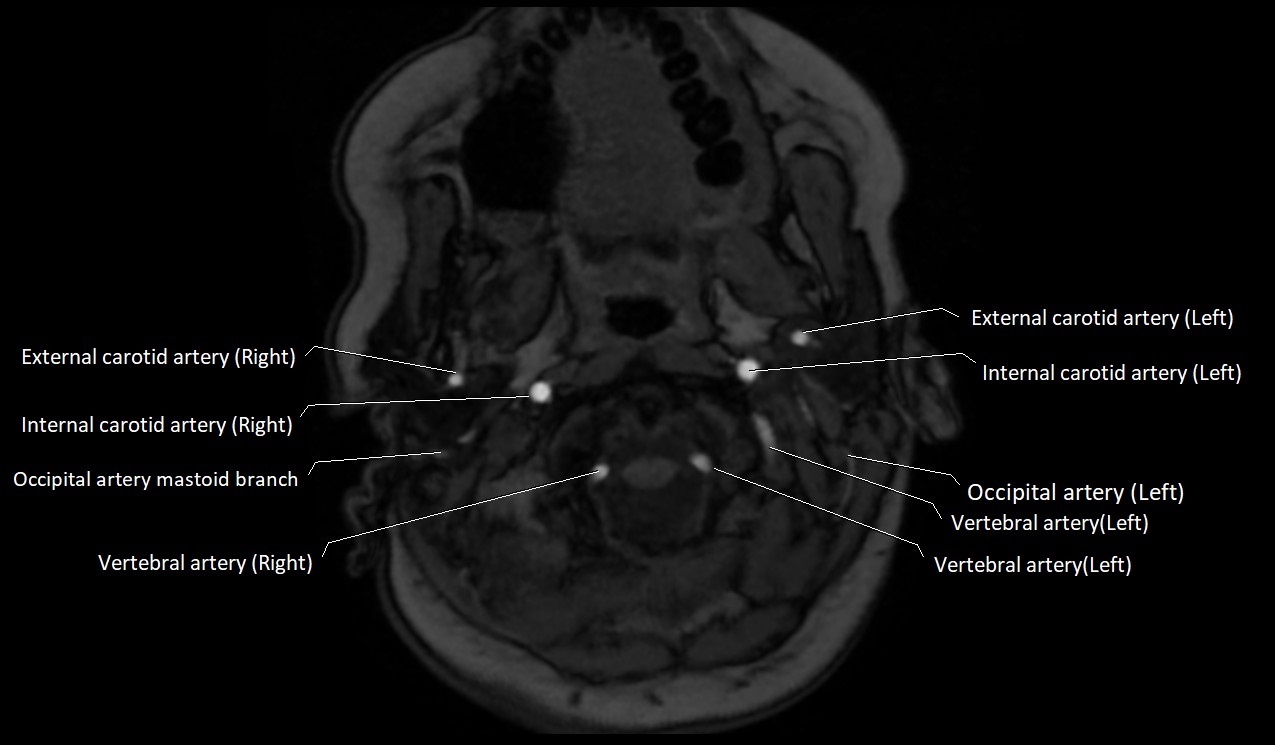

CT image

image